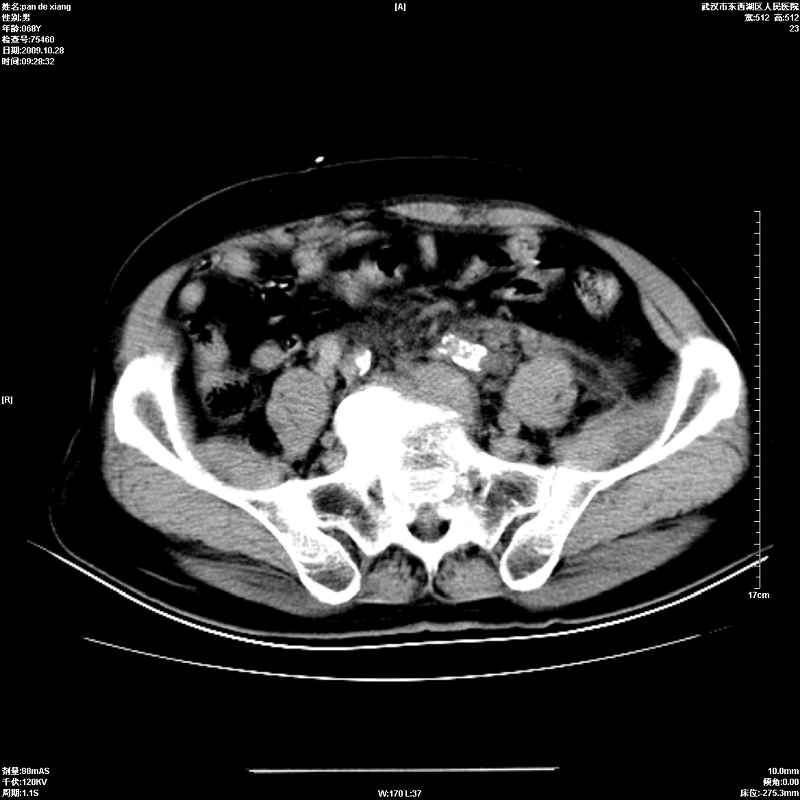

以下是引用杀毒软件在2009-10-28 20:41:00的发言:[br]结合临床考虑---白血病双肾改变或淋巴瘤。

以下是引用zxl51642在2009-10-29 9:59:00的发言:[br]结合临床“单克隆免疫球蛋白血症”,考虑双肾为继发损害并肾功能不全(尿中大量igg及少量iga、igm等大分子免疫球蛋白滤出所致继发损害),椎前软组织肿块为髓外造血。与浆细胞瘤有区别,平扫时有战友说的很清楚。